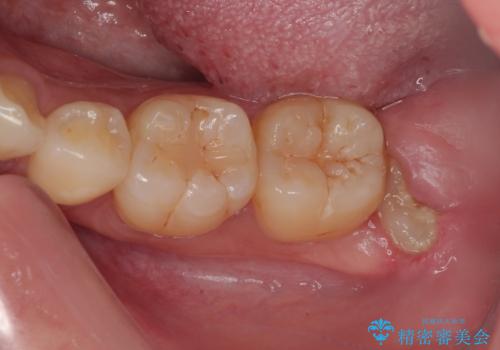

親知らずを抜きたい 親知らず抜歯

- 親知らずを抜きたいとのことで来院された患者様です。

CTで神経の位置などを確認し、抜歯術を行いました。